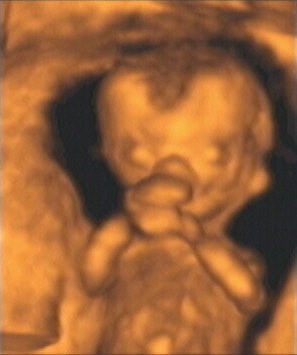

![]() |

| Figure 7, a 3-D ultrasound image of the fetus at 13 weeks gestation. Image courtesy of Stefano Ciatti, M.D. |